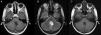

El tumor glioneuronal formador de rosetas del IV ventrículo es un tumor primario del sistema nervioso central introducido en el grupo de tumores glioneuronales en la clasificación de la OMS de 2007. Inicialmente se describió alrededor del IV ventrículo, pero recientemente se han publicados casos en distintas localizaciones. Presentamos 2casos de este raro tumor, ambos tratados quirúrgicamente. El primero en un varón de 41 años de edad, con síntomas típicos de lesión de fosa posterior; el segundo, en una mujer de 18 años de edad, con hallazgo incidental de lesión en fosa posterior que también fue tratada quirúrgicamente. Presentamos imágenes de resonancia magnética pre- y posquirúrgicas, aportamos imágenes histológicas de este tumor y realizamos una revisión de la literatura.

Rosette-forming glioneuronal tumor of the fourth ventricle is a primary central nervous system tumor introduced in the group of glioneuronal tumors in the WHO classification of 2007. Initially it was described around the fourth ventricle, but recently have been published cases in different locations.

We present 2cases of this rare tumor, both surgically treated. The first in a 41 year old man with typical symptoms of posterior fossa injury. The second in an 18 year old woman, with incidental finding of posterior fossa injury that was also surgically treated.

We present pre- and post-surgical magnetic resonance images, histological pictures of this tumor and we make a review of the literature.